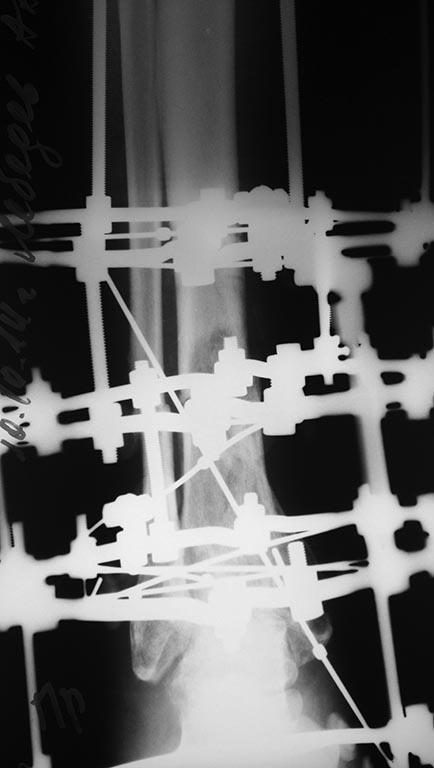

Небольшое уточнение: оперирован 1 августа, в ноябре снята база со стопы, в конце декабря демонтаж аппарата. Показания к снятию аппарата- заключение рентгенолога - консолидирующийся перелом, отсутствие патологической подвижности. Рана заживала около 3 -х месяцев условно первичным натяжением. Так как нет КТ руководствовались в основном рентген снимками.

Снимки при поступлении, спустя 2,5 месяца. Рентген снимки после снятия аппарата в архиве пришлю позже. Осылаю КТ от апреля.

Пациент 45 лет поступил с клиникой открытого перелома левой голени, обширной рваной раной передней поверхности голени.выполнен остеосинтез АВФ. Через 3 месяца снятие аппарата. Ношение ортеза с пневмокоррекцией.